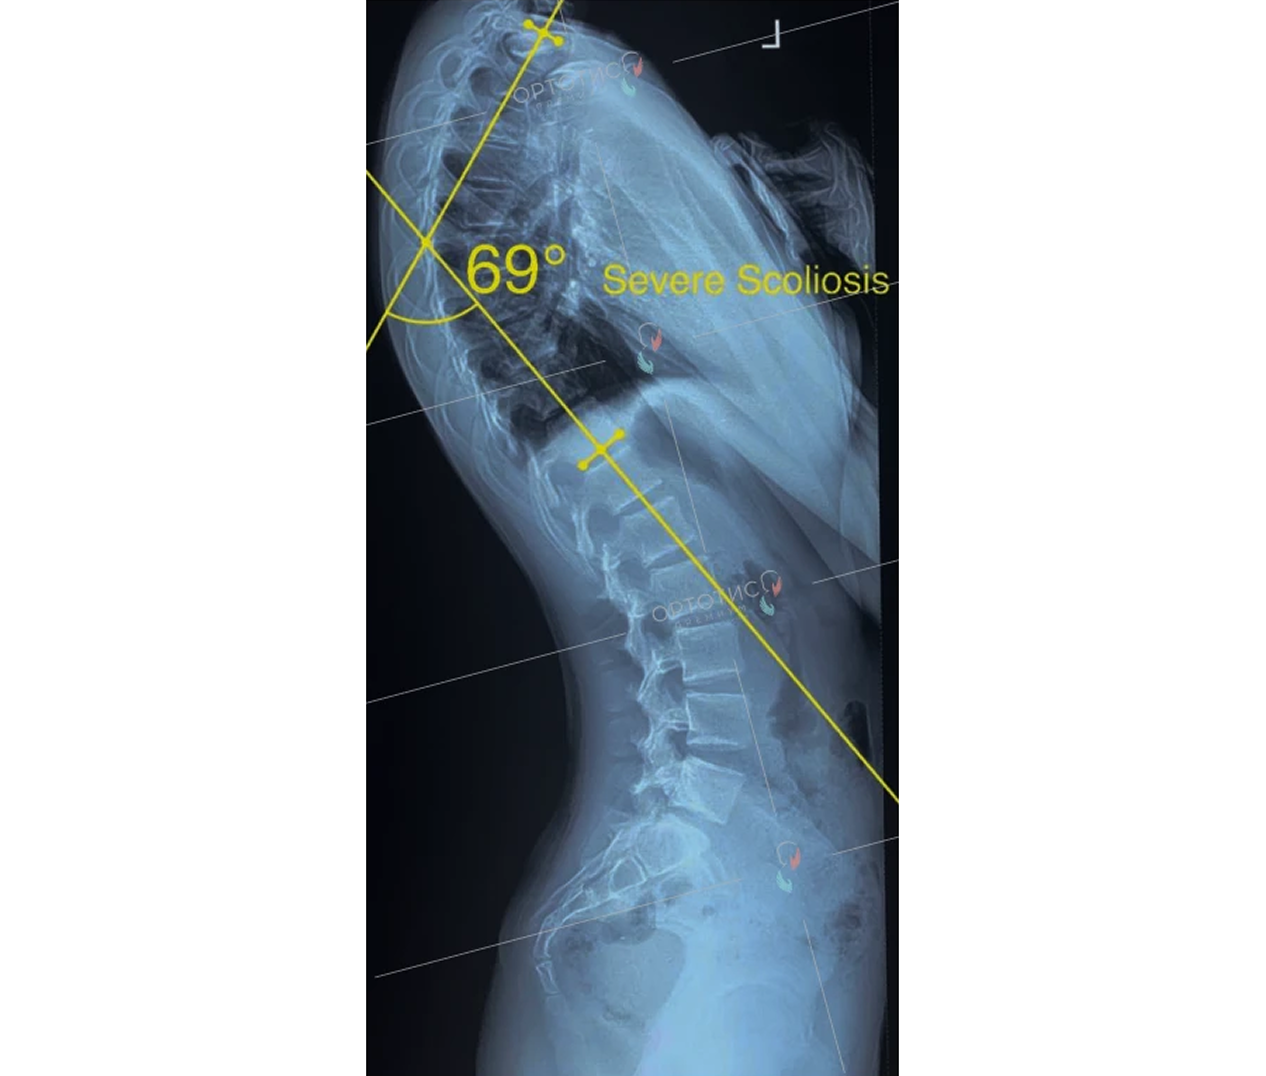

Корсет Шено в Алматы: эффективное лечение сколиоза

Корсет Шено — это «золотой стандарт» в лечении сколиоза у детей и подростков. В клинике Ортотис Центральная Азия в Алматы мы изготавливаем активные ортопедические корсеты, которые не просто удерживают позвоночник, а эффективно исправляют деформацию.

• Идиопатический сколиоз с углом искривления от 20° по Коббу;

• Быстро прогрессирующие формы деформации позвоночника;

• Кифосколиоз и другие нарушения осанки.

Мы используем высокоточное 3D-моделирование, что позволяет создать корсет, идеально соответствующий анатомии ребенка. Это обеспечивает максимальную коррекцию при сохранении мобильности. Наши техники-ортопеды в Алматы проводят регулярную коррекцию изделия по мере исправления позвоночника.